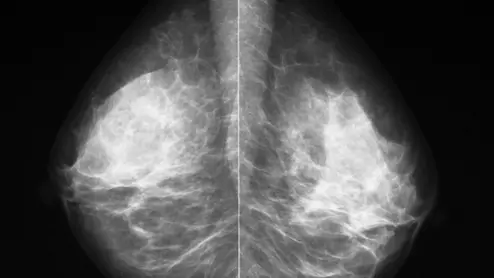

Thanks to AI, clinicians can use mammograms to do a lot more than identify signs of breast cancer. Researchers explored data from nearly 50,000 patients, presenting their findings in Heart.